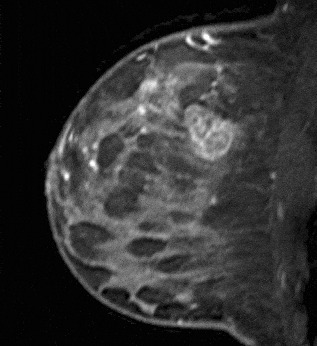

Figure 5. Lobulated mass. Pathology – Infiltrating ductal cancer.

Figure 6. Irregular mass. Pathology – Infiltrating ductal cancer.